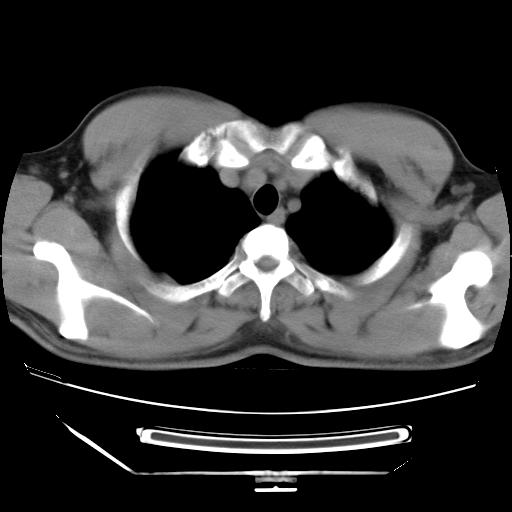

男,38岁,于2009年8月9日晚突发左侧胸痛,今x线提示左下肺阴影,为了明显确诊断,行ct检查,

血常规:嗜酸性细胞增高,单核细胞增高。

病灶发生在下叶,密度均匀,边缘模糊、毛糙,周围血管纹理增强扭曲改变,靠近胸膜处病灶胸膜反应明显。

支持考虑---球形肺炎。

左肺舌叶病变。主体病灶呈类圆形中心密度低,成液化趋势周边班片影分布

考虑肺脓肿